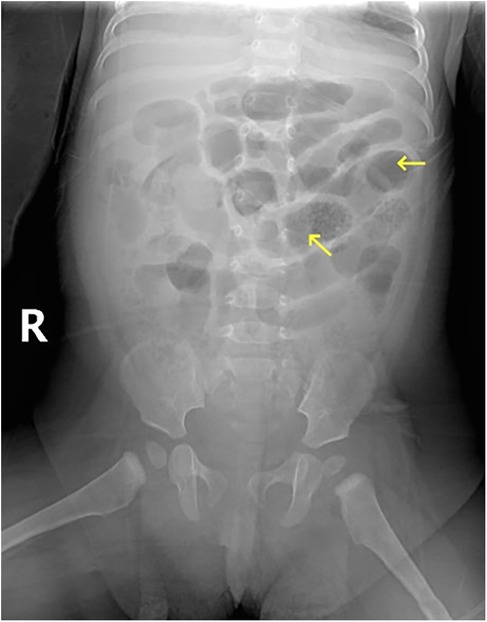

Congenital transmesenteric hernia, a rare internal hernia, is notoriously challenging to diagnose preoperatively due to nonspecific symptoms and inconclusive routine evaluations. In infants, early manifestations such as vomiting, irritability, and diarrhea often mimic acute gastroenteritis, leading to delayed recognition. Without timely intervention, progression to intestinal strangulation, necrosis, and shock significantly escalates treatment complexity and mortality risk. We report a case of a 6-month-old female infant with approximately 131cm of necrotic small bowel secondary to a giant transmesenteric hernia. This case illustrates the clinical trajectory, diagnostic pitfalls, and surgical management, highlighting the imperative for early suspicion and intervention. Critical analysis of this case underscores that prompt surgical correction is pivotal to mitigate morbidity and mortality in such scenarios. Enhanced clinician awareness of this condition and its subtle early signs could improve outcomes in pediatric patients.